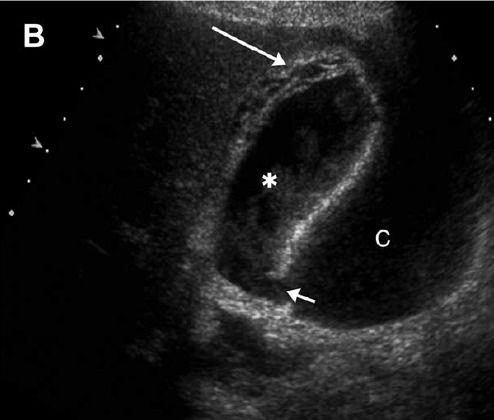

超声表现:胆囊增大,结石,胆壁增厚、充血,胆周积液、超声墨菲斯征阳性(图 1)。当胆囊结石、囊壁增厚、超声墨菲斯征阳性三种表现同时出现时,诊断急性胆囊炎阳性预测值为 94%。

图?1 72 岁男性急性胆囊炎,墨菲斯征(+),超声表现为胆囊增大,宽径>4 cm,胆壁不规则增厚(白色箭头),颈部结石嵌顿(黑色箭头),周围出现脂肪回声、伴炎性变(*)90%~95% 的急性胆囊炎伴结石,超声表现为强回声伴后方声影,特别是直径大于 3 mm,后方出现闪烁伪像。结石嵌顿时(图 1),改变体位结石不移动。胆囊扩张多由胆管阻塞引起。正常胆囊长径可达 10 cm,宽径<3 cm,宽径增大更有意义。急性胆囊炎通常胆壁增厚>3 mm、毛糙、层次欠清。胆囊壁测量应在前壁垂直进行(图 1)。

图?2 ?图 A 为60 岁男性坏疽性胆囊炎,右上腹疼痛 7 天,发热,败血症。超声表现为胆囊增大、胆泥淤积(*),胆囊壁不连续(长箭头),黏膜剥离(弯曲箭头),周围相邻肝内可见?4.6 cm×5.5 cm 脓肿(短箭头);图 B 示另一患者胆囊颈部粘膜中断伴胆囊周围积液(c)。胆囊壁增厚,条纹状弱回声带,胆汁淤积